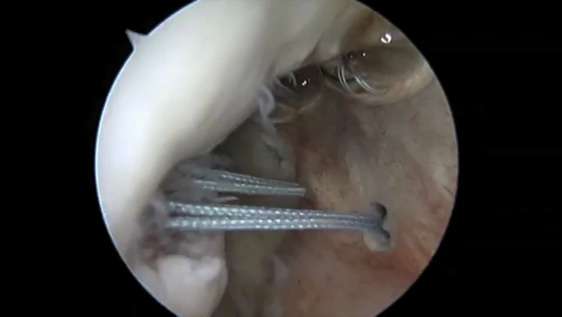

Una delle tecniche più utilizzate in caso di instabilità della spalla è la capsuloplastica artroscopica associata al remplissage in cui il Dr. Consolini è specializzato con oltre 150 interventi negli ultimi 5 anni.

Gli specialisti di spallaonline sono in grado nello stesso intervento di reinserire il complesso cercine-legamenti alla glena e di chiudere l’incisura di hill-sachs utilizzando ancorine di fissazione in tessuto di soli 2 mm. -intervento di Bankart plus – In caso in cui il danno ai legamenti o il danno osseo fossero di entità eccessiva si può eseguire un intervento a cielo aperto e in anestesia generale detto di Latarjet.

L’artroscopia consiste nell’accesso all’articolazione attraverso piccole incisioni e strumenti dedicati, con controllo attraverso microtelecamera. In questo modo, i muscoli non vengono incisi, e, in caso di pazienti affetti da danno solo capsulo-legamentoso questa tecnica è particolarmente adatta.In questo intervento le lesioni delle strutture “molli” (capsula e legamenti), vengono riparate con l’ausilio di piccole ancorette e di fili di sutura.In caso invece di danno anche osseo (sia a livello della testa dell’omero che della scapola), in genere più frequente in casi di instabilità recidivante, si opta per un intervento “tradizionale”, che prevede un’incisione chirurgica di 4-5 cm e la trasposizione di piccoli innesti ossei con l’obiettivo di ripristinare una corretta anatomia e di creare una barriera alla fuoriuscita della spalla.